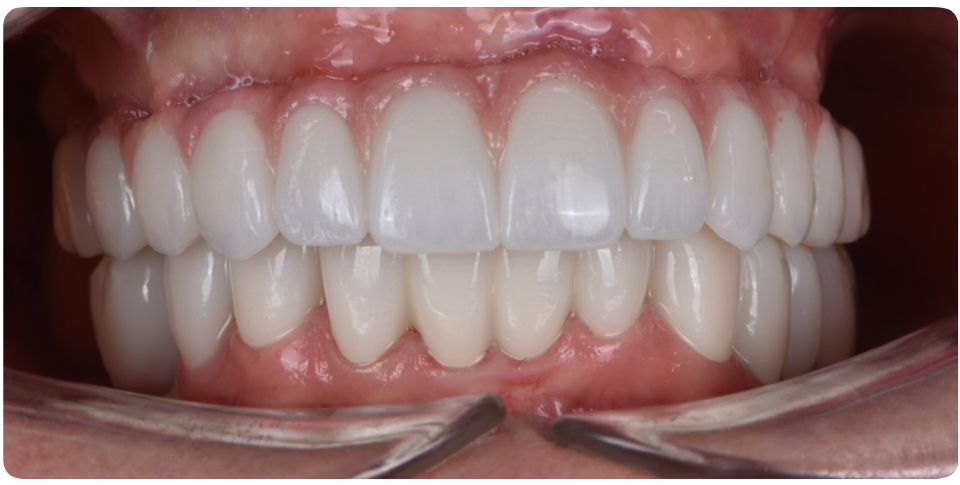

All on 4 All On 6 Implants

All on 4 or all on 6 treatment concepts is a graft less solution that provides patient with a fixed full arched prosthesis on the day of the surgery.

This treatment concept was developed to maximize the use of available remnant bone in atrophic jaws, allowing immediate function and avoiding regenerative procedures that increase the treatment costs and patient morbidity, as well as the complications inherent to these procedures

Advantage – graft less solution, immediate form and function, life changing, scientifically proven, very high success rate